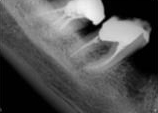

antes depois